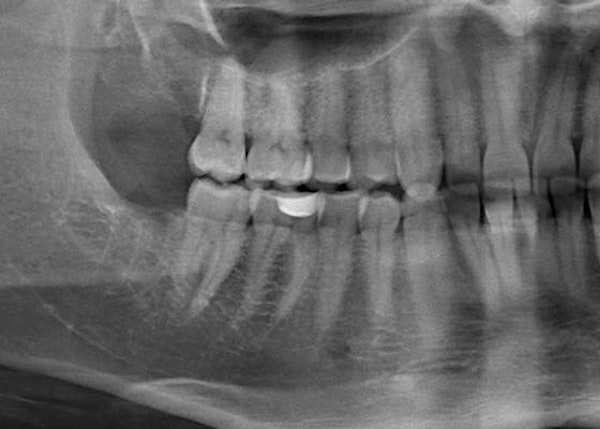

CT scans give our dentists a closer look at the visible parts of your teeth as well as the tooth roots, blood vessels, soft tissues, and other parts of the mouth that the eye can't see. These scans give us a more detailed view of the position of your wisdom teeth when they haven't yet erupted. We can also take digital impressions of your teeth using our intraoral scanner. We aim to give you an accurate view of your smile and improve your overall wellness by using this technology and other advanced tools at our Vancouver dental office.

This is why visiting your dentist regularly is so important. They can use X-rays to watch as your teeth emerge and determine if they'll be a problem in the future or if they can stay.